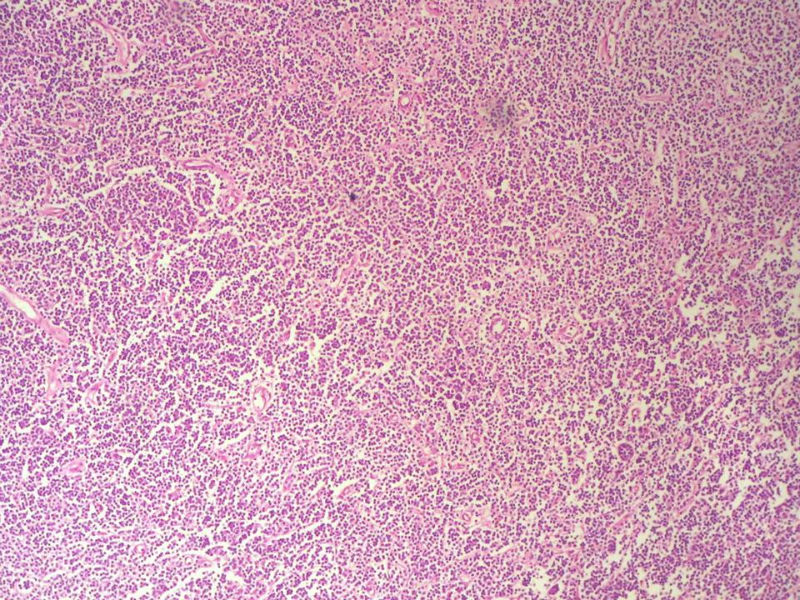

男,49岁,左眼睑球结膜下肿物2个月,手术切除。检查肿块3X2X2厘米,切面灰红色,质软。

本例是发生在特殊部位“结膜下”,HE肿瘤细胞形态形态一致,形似单核样B细胞。B细胞标记若明确阳性,诊断MALT是挺合理的。

HE:  1.MALT粘膜相关淋巴瘤:本例部位很特殊,位于“结膜下”,考虑MALT很合理;但本例镜下细胞形态很一致,诊断MALT是有难度的。

2. SLL小细胞淋巴瘤:就细胞形态而言,有相似之处,考虑SLL也有道理;但如果在没有发现淋巴结,肝,脾,骨髓或外周血具有病变的前题下,原发于结膜的SLL可能是少见的。

3.套细胞淋巴瘤:细胞大小及一致性比较符合;但本例核太规则了,套细胞淋巴瘤很难有这么规则的圆形或椭圆形。

4.滤泡性淋巴瘤: 可能性更小,暂时不考虑。

淋巴样细胞。细胞形态单一,细胞小。主要鉴别:

1)粘膜相关淋巴组织淋巴瘤

2)小细胞性淋巴瘤/慢性淋巴细胞性白血病

3)套细胞淋巴瘤

形态结构与细胞大小,似不支持滤泡性淋巴瘤。

淋巴瘤  细胞小  形态单一  主要考虑小B细胞淋巴瘤